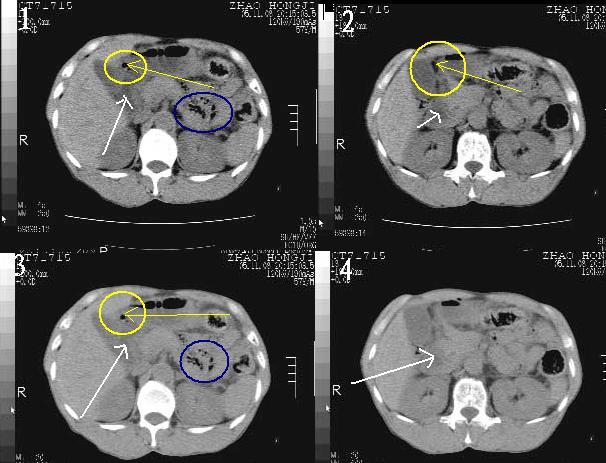

意见:12指肠(球部)穿孔可能性大。

肝缘见少许气体,胰尾部见少许气体包饶(蓝色圈),12指肠上部或球部邻近胆囊周边也可见少许气体影(黄色圈),并忖托出胆囊壁,12指肠远段肠道内未见明显气体(白色箭)。

消化道穿孔。12指肠球部周和胰周积气考虑12指肠穿孔可能性大。

入院3小时后行剖腹探查术,见腹腔内大量脓性混浊液约1000ml,十二指肠球部溃疡穿孔,溃疡面约2.5x2cm,穿孔直径约0.6cm。胃内容物外益,周围组织炎性水肿明显。行十二指肠穿孔修补术。术后诊断:

1、十二指肠溃疡穿孔

2、弥漫性腹膜炎

对于少量的腹腔游离气体,ct检查较普通透视有绝对的优势,它不仅可以看到肝脏前上缘的气体,而且还能够看到小网膜区的游离气体。从而可以肯定诊断。各位分析战友的很好,感谢大家的参入!